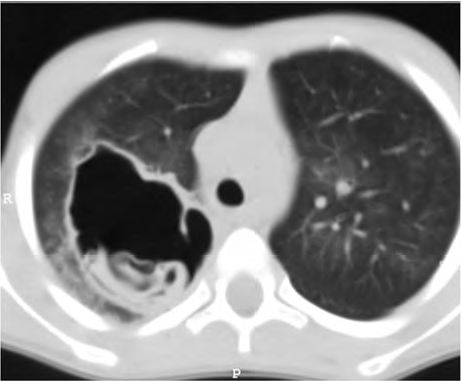

Determinado paciente de 49 anos de idade, morador em zona rural, iniciou com quadro de tosse importante, com piora progressiva, de início há dois meses, associada a alguns episódios de vômica. Refere febrículas na última semana. O paciente é tabagista leve, trabalha com criação de ovelhas e mora em casa com cachorros e gatos. Nega viagens internacionais recentes. Não foi encontrada nenhuma alteração no exame físico. Verificaram-se FC = 80 bpm, FR = 20 irpm e SatO2 = 99% em ar ambiente. A tomografia de tórax apresenta uma lesão cística de paredes espessas e conteúdo heterogêneo em seu interior, conforme representado na imagem a seguir.

Acervo Pessoal